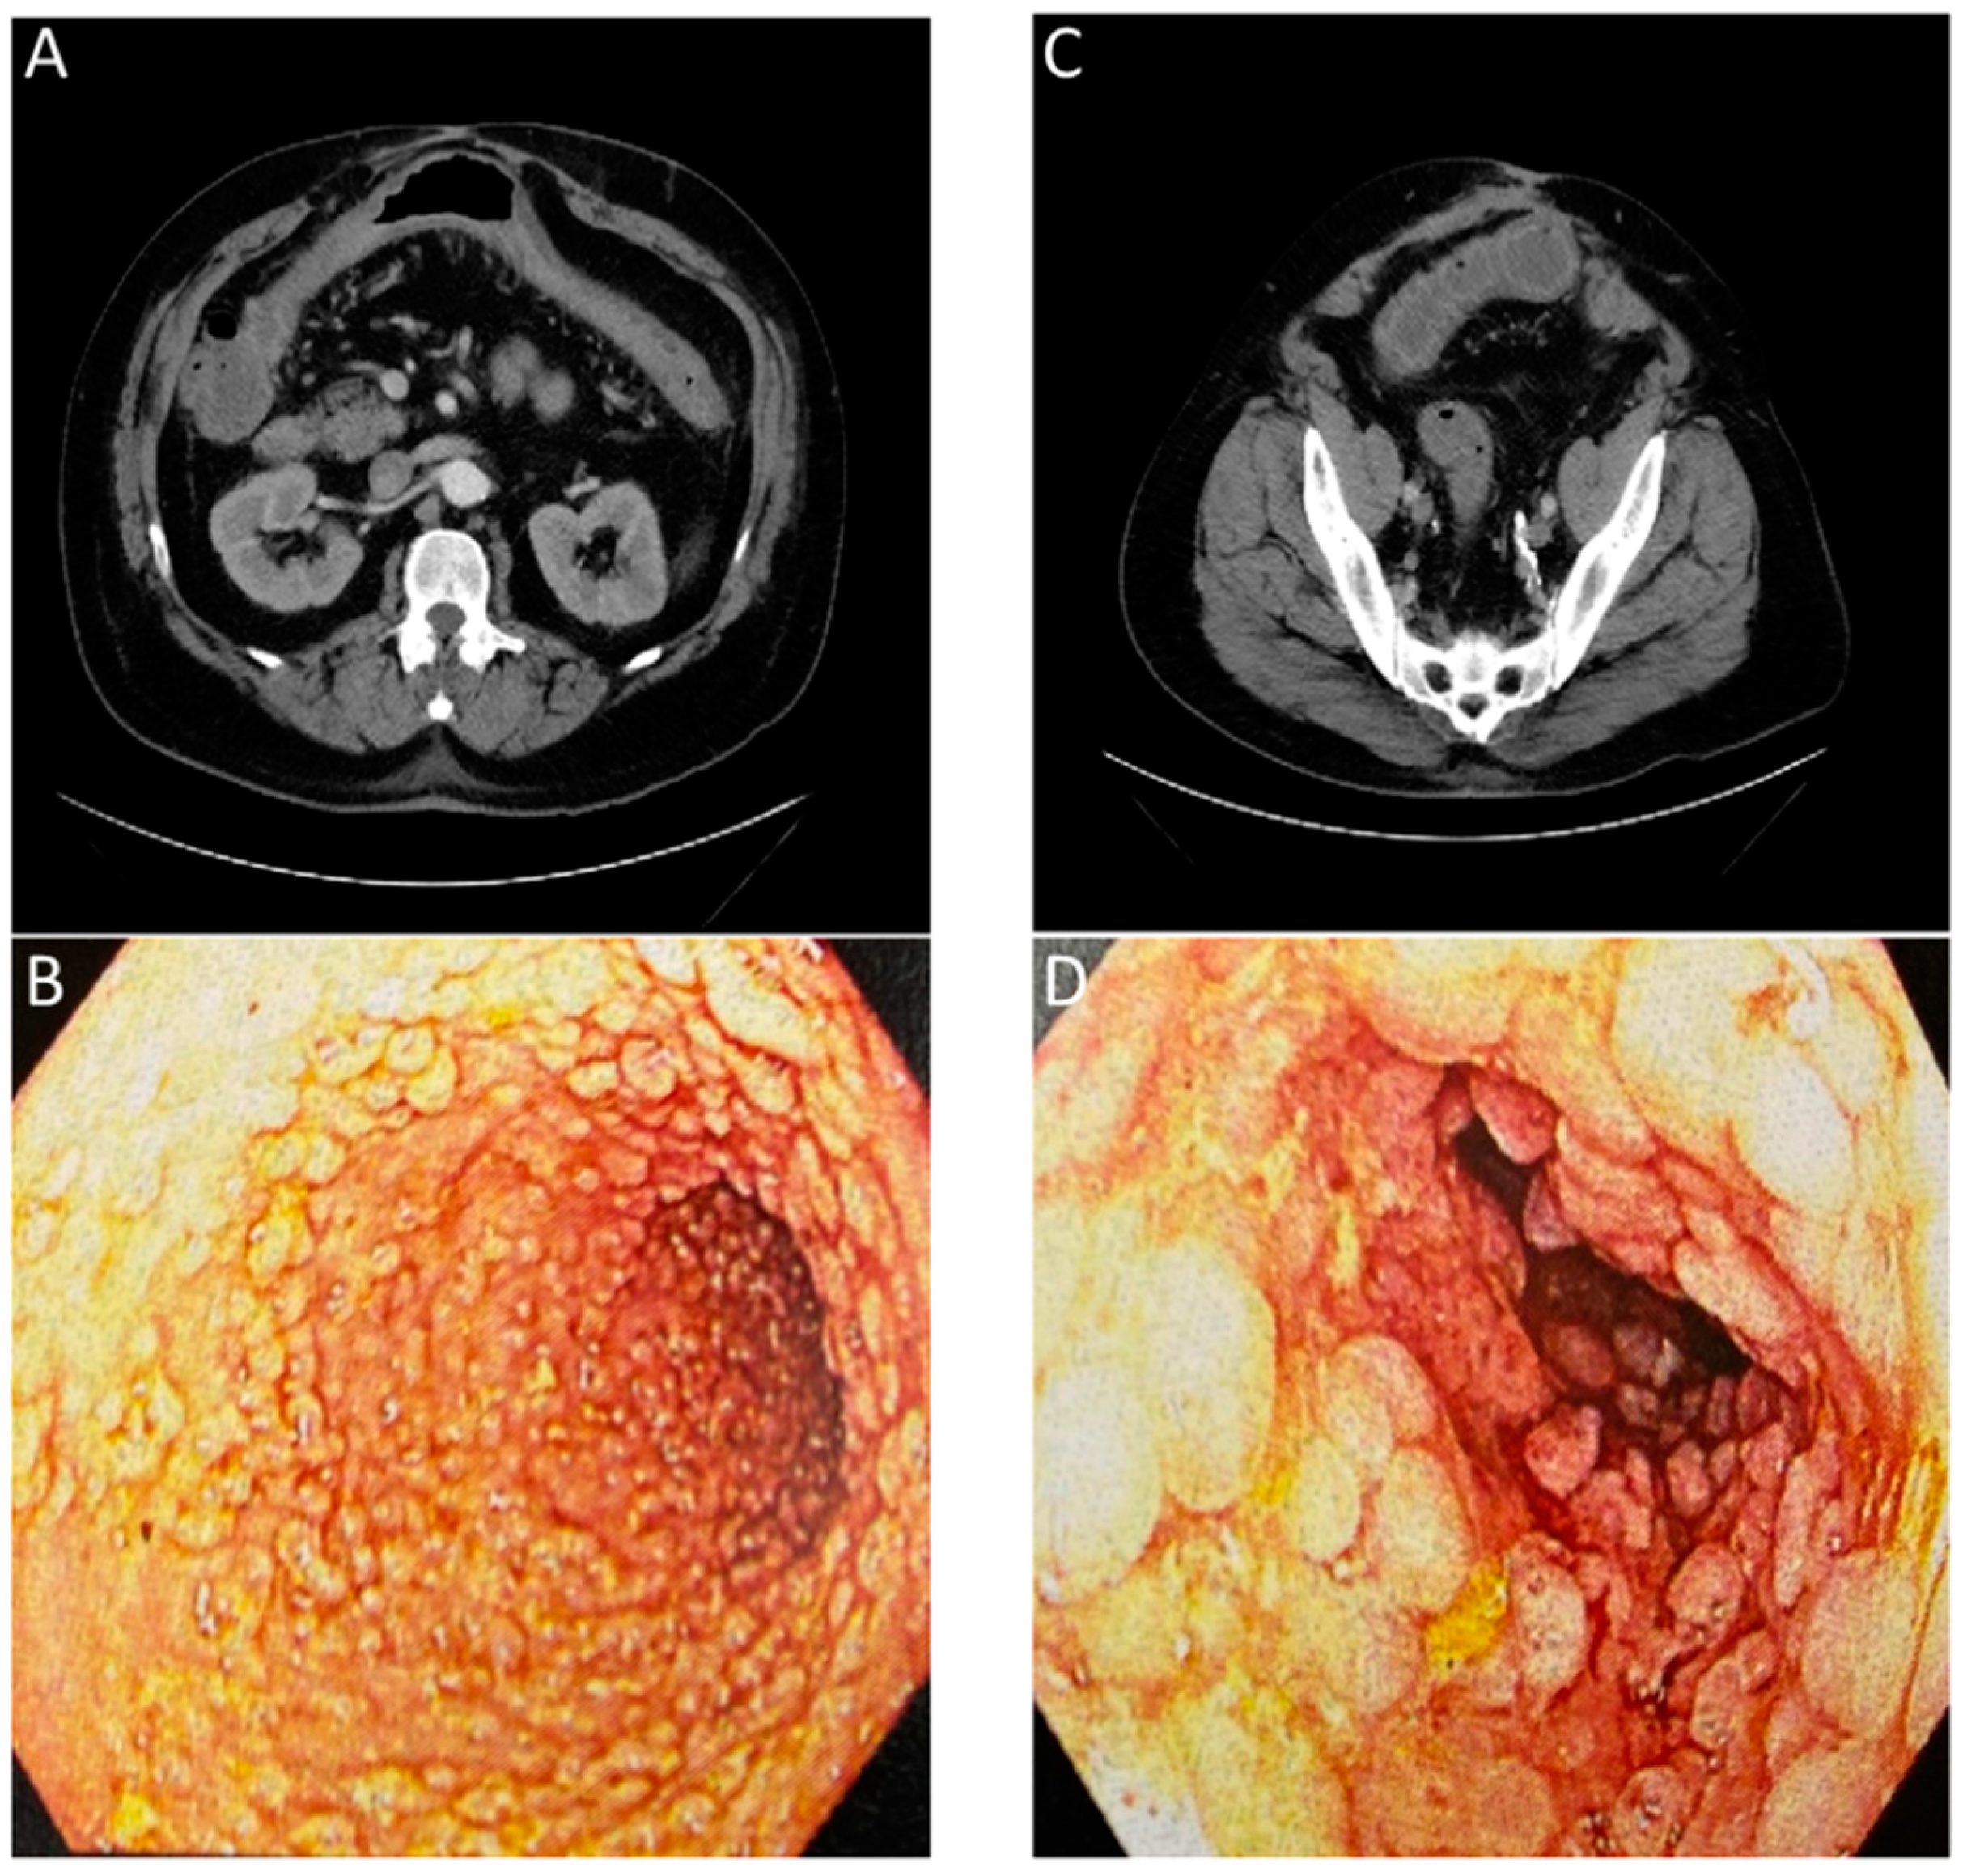

- Frickenstein, A.N.; Jones, M.A.; Behkam, B.; McNally, L.R. Imaging Inflammation and Infection in the Gastrointestinal Tract. Int. J. Mol. Sci. 2019, 21, 243. [Google Scholar] [CrossRef]

- Catalano, O.A.; Wu, V.; Mahmood, U.; Signore, A.; Vangel, M.; Soricelli, A.; Salvatore, M.; Gervais, D.; Rosen, B.R. Diagnostic Performance of PET/MR in the Evaluation of Active Inflammation in Crohn Disease. Am. J. Nucl. Med. Mol. Imaging 2018, 8, 62–69. [Google Scholar]

- Le Fur, M.; Zhou, I.Y.; Catalano, O.; Caravan, P. Toward Molecular Imaging of Intestinal Pathology. Inflamm. Bowel Dis. 2020, 26, 1470–1484. [Google Scholar] [CrossRef]

- Perlman, S.B.; Hall, B.S.; Reichelderfer, M. PET/CT Imaging of Inflammatory Bowel Disease. Semin. Nucl. Med. 2013, 43, 420–426. [Google Scholar] [CrossRef]